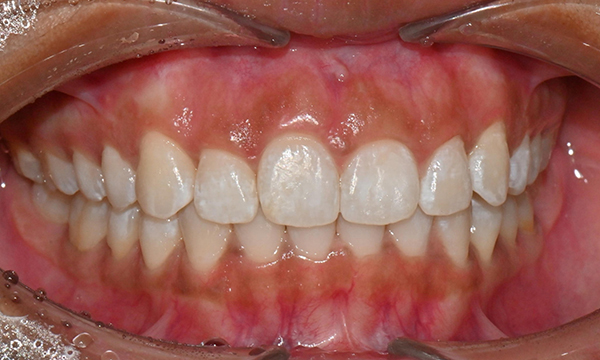

교정 마무리 후 사진 (2025.8)

최종적으로 교정을 마무리한 후에는

위아래 치아 배열이 훨씬 가지런해졌고,

깊게 물렸던 과개교합도 크게 개선되었어요.

왼쪽 작은 어금니는 목표에서 제외했던 만큼,

아직 완벽하게 교합이 맞지는 않았지만,

치료 자료를 전달해 드리고 추후 본국으로 돌아가서

남은 치료를 이어서 받기로 하셨답니다.

한 가지 더:

오른쪽 위 앞니는

원래도 잇몸이 조금 내려가 있었어요.

그래서 교정을 끝내면 좌우 잇몸 높이가

다를 수 있다는 점을 미리 말씀드렸고요.

나중에 치은성형술로 잇몸 높이를 맞추면

더 예뻐 보일 거라고 추천해 드렸어요.